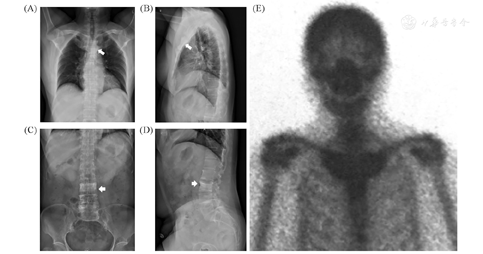

骨密度及影像学检查:双能X线吸收测定法(DXA)示腰1至腰4、股骨颈、全髋骨密度值分别为0.588、0.632、1.069、0.711、0.678、0.624 g/cm2,对应的T值分别为-3.7、-3.9、-0.7、-3.6、-2.1、-2.7,其中腰3椎体骨密度明显更高。胸椎正侧位X光片示胸骨、双侧锁骨近端及第1肋局部稍增粗、骨质密度增高(图1A、图1B),腰3椎体骨密度较其他椎体明显增高(图1C、图1D),胸11、腰3、5椎体楔形变。骨显像示双侧胸锁、第一肋胸关节及胸骨柄骨代谢增高(图1E)。双上肢超声:各关节、骨无明显异常,右侧肱二头肌长头腱腱鞘积液。

注:(A)(B)患者胸锁关节、第一肋关节及胸骨柄骨肥厚;(C)(D)腰3椎体骨密度增高;(E)骨显像提示患者胸骨柄及双侧胸锁关节有放射性核素浓聚,为SAPHO综合征特征性的"牛头征"